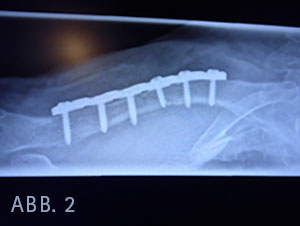

Die vierte Schraube in der LC - Platte (Locking Compression Plate) von medial perforiert die Gegenkortikalis deutlich (Abb. 2) und liegt 5,25 cm vom Akromioklavikulagelenk (AC) und 8,25 cm vom Sternoklavikulagelenk (SC) entfernt.

Um die Topografie des Gefäß- Nervenbündels und die Lage der im Röntgenbild überstehenden Schraube in der Klavikula (Abb. 2) zur Arteria subclavia besser beurteilen zu können, erfolgte an einer unfixierten Leiche einer Körperspenderin eine Plattenosteosynthese der Klavikula entsprechend den am Röntgenbild ermittelten Angaben und die Präparation des Gefäß- Nervenbündels.

Nach Resektion des Musculus subclavius wird deutlich sichtbar, dass die Schraubenspitze sich 7,25 cm vom AC - Gelenk und 8,25 cm vom SC - Gelenk befindet und somit lateral der Vasa sublavia, die 5,5 - 7,5 cm vom SC - Gelenk entfernt unter dem Schaft der Klavikula hindurchziehen.

Die Schraube ist unterhalb der Klavicula sichtbar (Abb. 3), weil die Klavikula an dieser Stelle nur ca. 12 mm dick ist und eventuell der Winkel des Bohrlochs etwas anders lag. Auch könnte die Schraube etwas tiefer in das Bohrloch der Platte gerutscht sein.

Zusammenfassend ist eine Arrodierung der Gefäße durch die auf dem Röntgenbild zu lang erscheinende Schraube eher unwahrscheinlich, weil die Schraube lateral der Gefäße platziert wurde. Allerdings würden die Bohrlöcher für die zweite und dritte Schraube über den Gefäß- Nervenstraße liegen (Abb.3). Es könne nicht beurteilt werden, ob die Eintauchtiefe des Bohrers lege artis war und ob beim Bohren oder beim Anlegen des Hohmann - Hebels die Gefäß- Nervenstraße verletzt wurde.